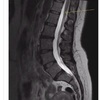

spinous process, pedicle, cauda equina, conus medullaris

conus medullaris

Highlighted structure

Vertebral body

77

78

Intervertebral disk